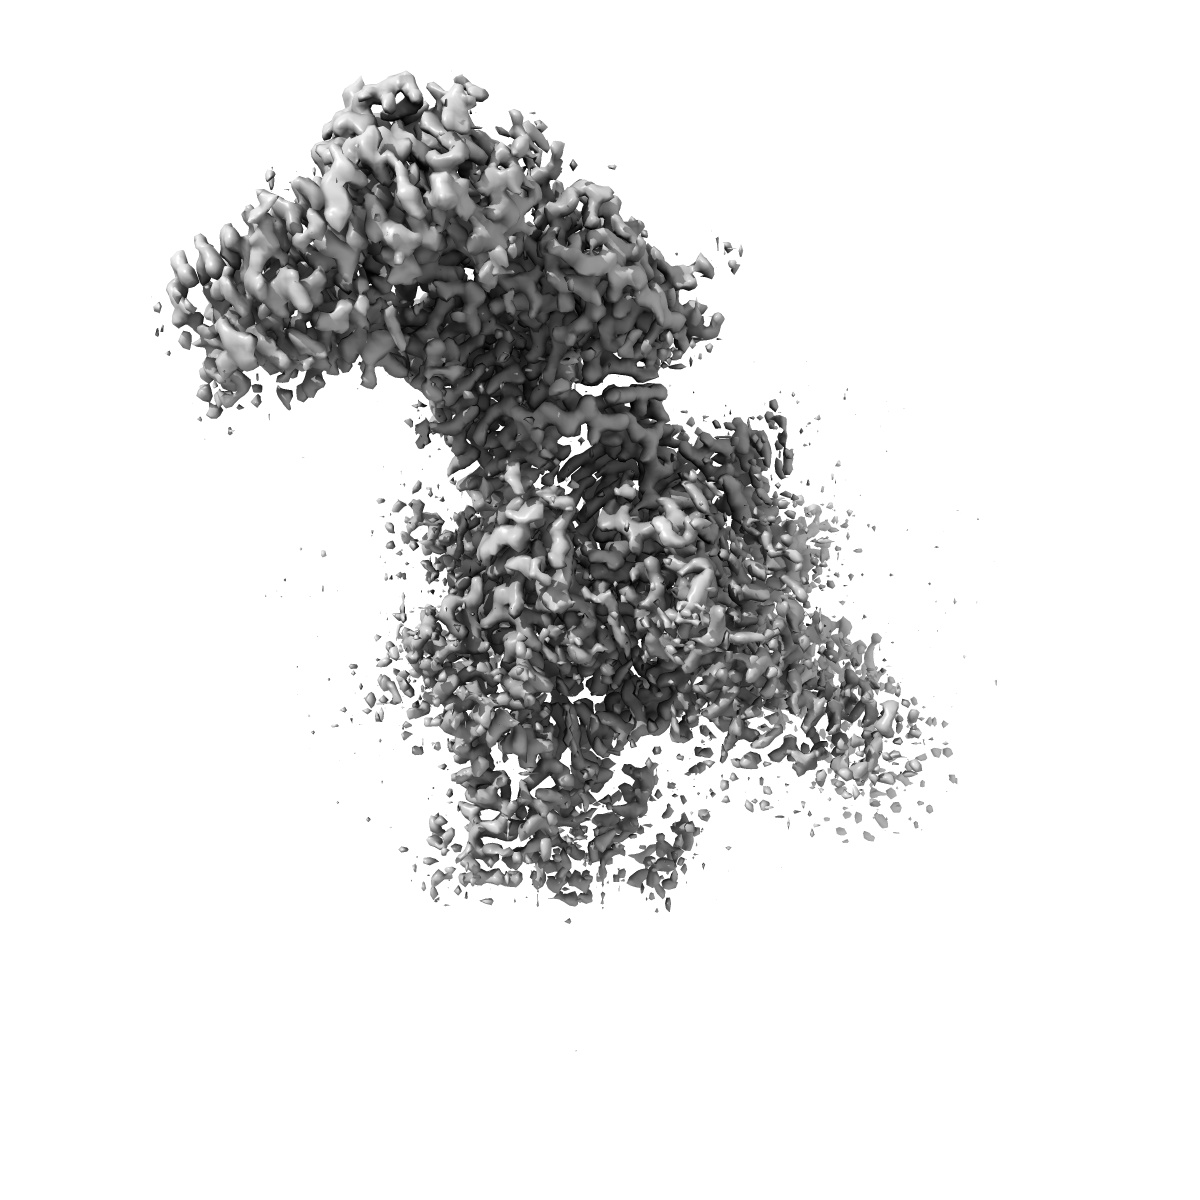

Human L-type voltage-gated calcium channel Cav1.2 in the presence of amiodarone and sofosbuvir at 3.3 Angstrom resolution

Structural basis for human Ca v 1.2 inhibition by multiple drugs and the neurotoxin calciseptine.

Gao S, Yao X, Chen J, Huang G, Fan X , Xue L , Li Z, Wu T , Zheng Y, Huang J, Jin X, Wang Y, Wang Z, Yu Y, Liu L, Pan X, Song C, Yan N

(2023) Cell , 186 , 5363 - 5374.e16